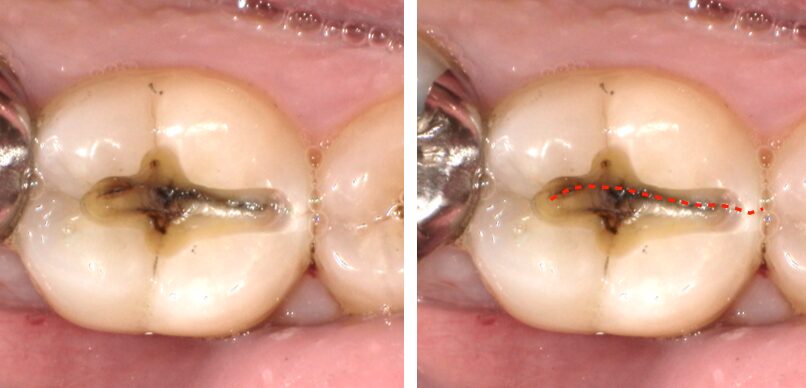

その中でも今回注目したいのが「歯の破折」です。

歯の破折

実は歯が割れることは神経を抜いている歯には比較的起こることがあります。

神経が残っている歯が割れることで知覚過敏のような症状を起こすことがあるのですが

神経が残っている歯は柔軟で強度があるため、割れることは実はほとんどありません。

早期接触は歯の破折の前の段階

それだけでなく、噛むたびに負荷がかかり続けることで歯が疲労し

最悪の場合は歯の破折を引き起こす場合があります。